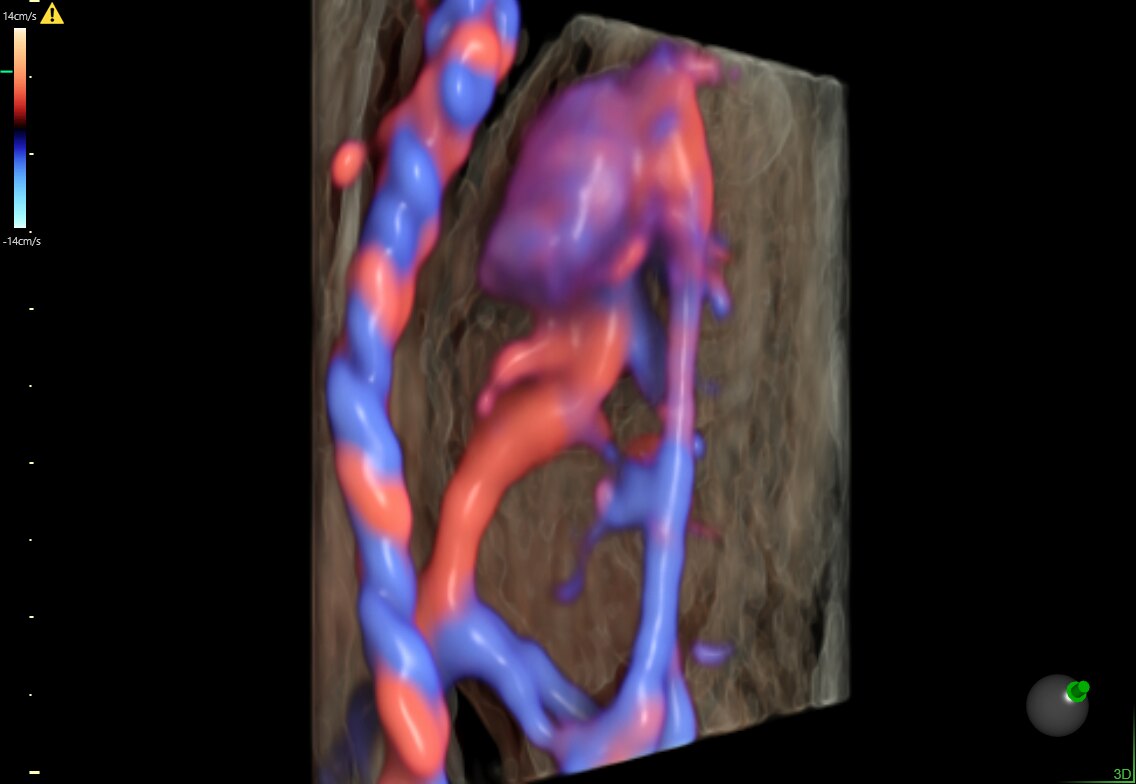

15-week fetal circulatory system with eSTIC and HD-Flow™